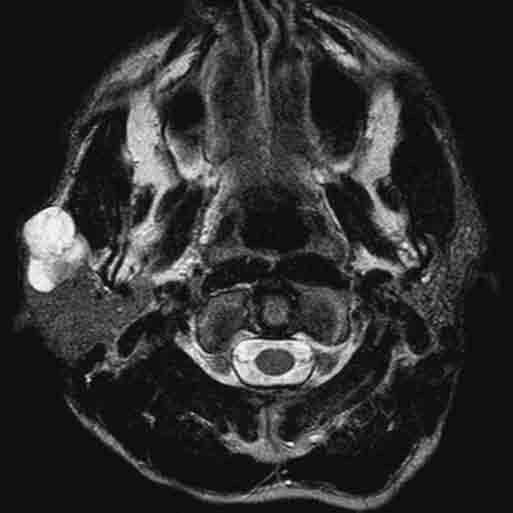

A part dans le cas des lymphomes et des tumeurs métastatiques, le traitement idéal des tumeurs parotidiennes bénignes ou malignes est chirurgical. Dans les rares cas où l’état de santé du patient est une contre-indication à la chirurgie, on préconisera un traitement conservateur basé sur le suivi clinique et radiologique. Lors de votre consultation, une anamnèse détaillée ainsi qu’un examen clinique minutieux permettront au Dr Yousefpour de cerner au mieux votre condition. Il complétera sa mise au point en demandant des examens complémentaires tels qu’une IRM (imagerie par résonance magnétique également appelée RMN ou résonance magnétique nucléaire) ainsi qu’une biopsie écho-guidée (examen lors duquel le radiologue performera une biopsie guidée par échographie). Au terme de cette mise au point le Dr Yousefpour discutera avec vous le diagnostic, le pronostic ainsi que les différentes options de traitement.